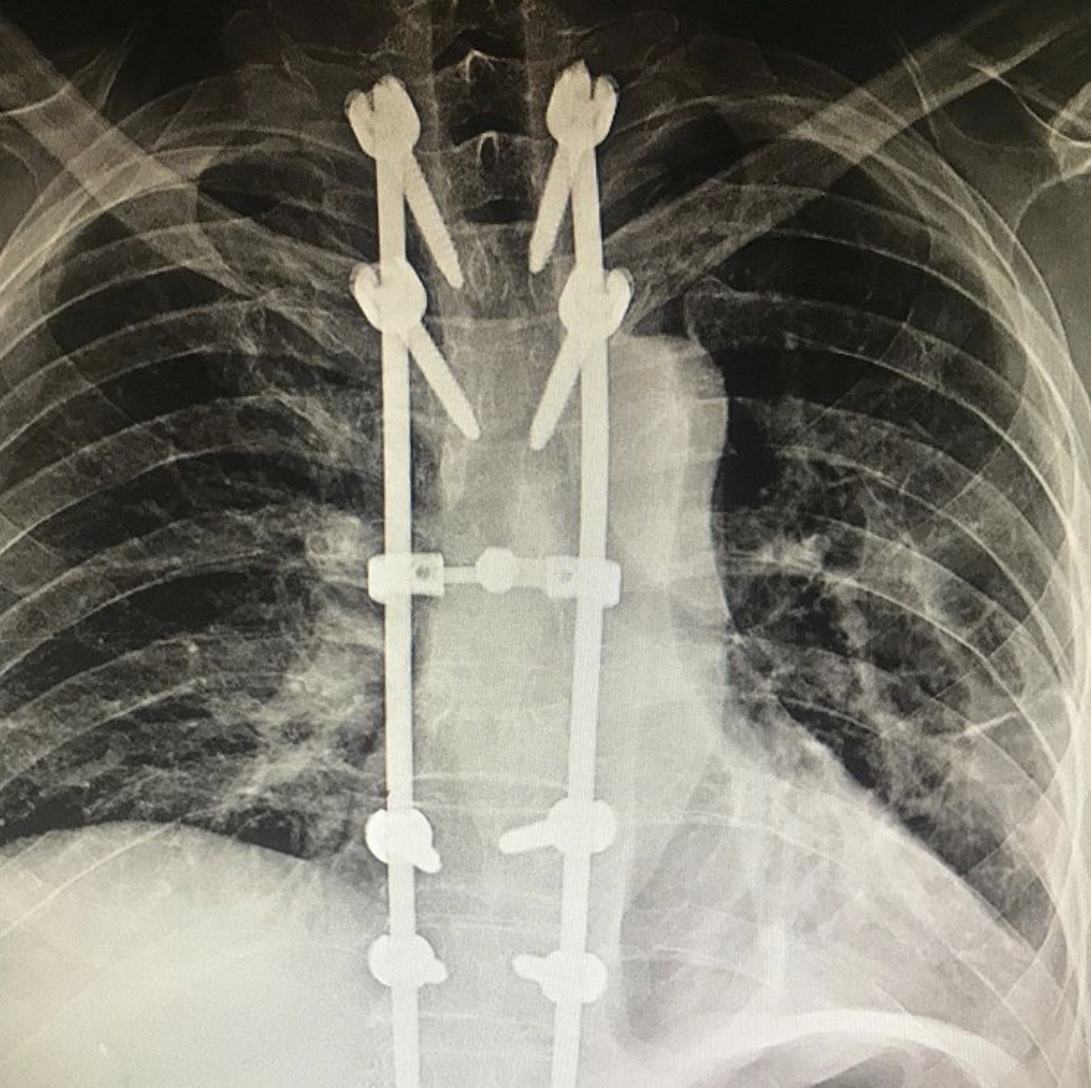

После тщательного обследования пациенту была выполнена реклинация и задняя стабилизация транспедикулярной системой: транспедикулярный спондилодез Д3-Д10.

Спондилодезом называют хирургическое вмешательство, являющееся разновидностью артродеза. Целью операции является обездвиживание одного или нескольких позвоночно-двигательных сегментов. Это достигается за счет установки специальных конструкций, которые надежно фиксируют между собой подлежащие сращению позвонки. В результате они со временем они прочно срастаются, что полностью исключает возможность движения и раз